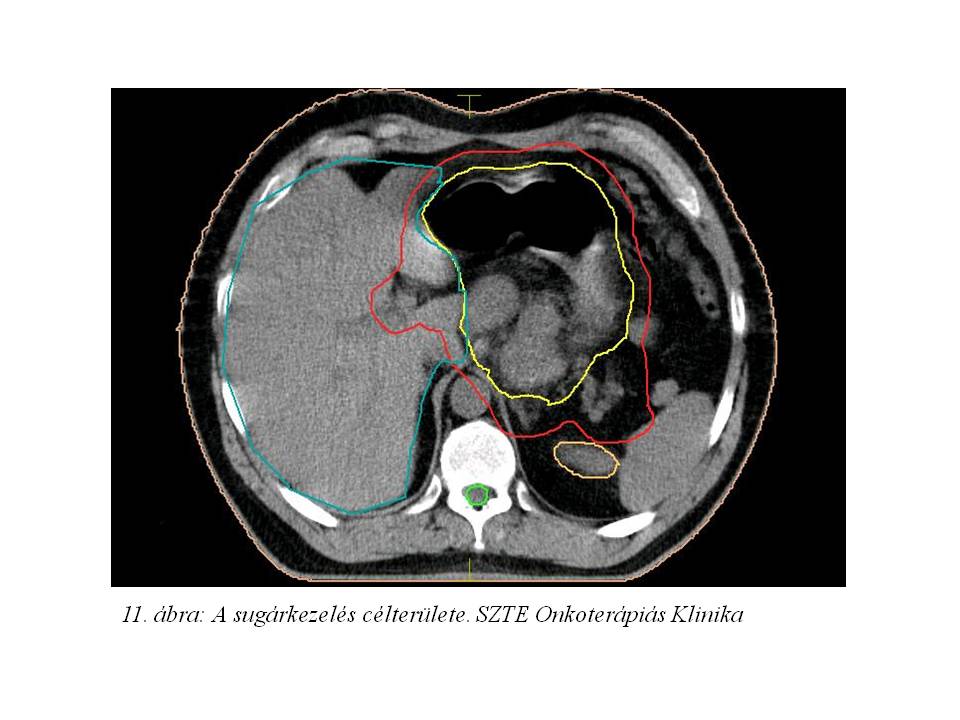

2014.05.15-én gasztro-intestinális onkoteam a tumor elhelyezkedése miatt a folyamat operábilissé válását nem tartotta valószínűnek, és további palliatív onkológiai kezelést javasoltak. A felépülést követően státuszrögzítő CT-vizsgálat történt (2015.10.18. 10. ábra), mely a hasi státusz progresszióját írta le, de távoli metasztázis nem igazolódott. A folyamat aktiválódását jelezte az is, hogy az acantosis nigricans ismét aktiválódott. A beteg általános állapotát és kérését figyelembe véve, 2014.11.10-12.19-ig definitív/konverziós célú sugárkezelést adtunk a GEJ tumorra (célterület 11. ábra), a perigastricus térre, a truncus coeliacus nyirokrégióra, a lép- és májkapu, paraaorticus régióra; az 1. és 5. héten 5FU+leucovorinnal sugárérzékenyítve. A sugárkezelés megkezdésekor vérképét vörösvértest transzfúzió adásával rendeztük, ezt követően vérképe stabil volt, egyéb mellékhatás nem jelentkezett.